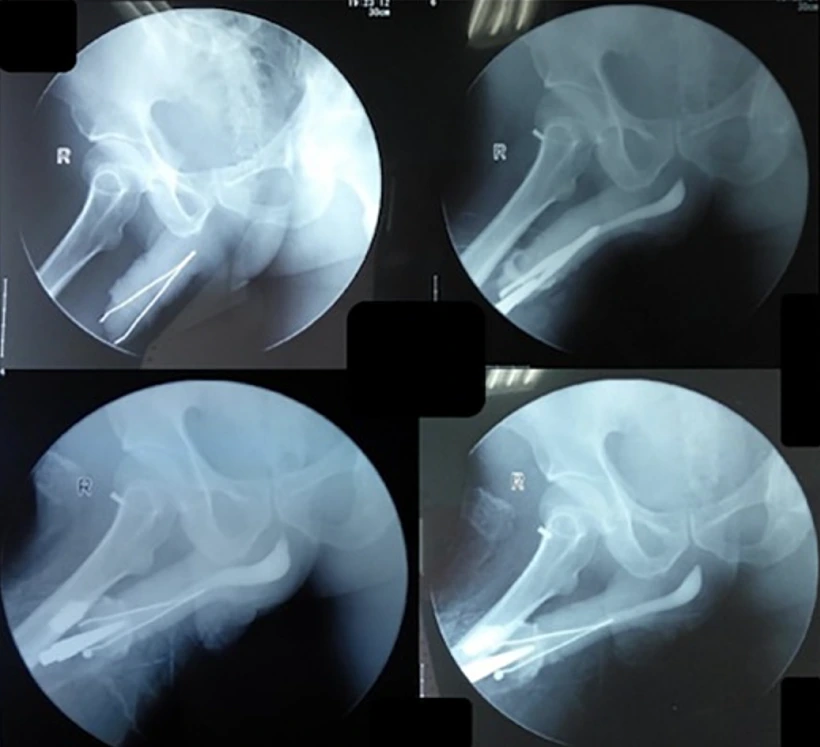

כאשר הרופאים גילו את העצם הזר שחדר לתוך קצה איבר מינו, הם הופתעו לגלות שהוא עדיין היה מסוגל להטיל שתן, אם כי בכאב ובקושי רב. צילומי הרנטגן חשפו את מלוא היקרף הבעיה, שכן הפינצטה הייתה תקועה בחוזקה בדרכי השתן שלו.

הרופאים נאלצו לבצע הליך חילוץ עדין בהרדמה. הם חתכו חתך קטן על איבר המין על מנת להרחיב את פתח השופכה ולהסיר את הפינצטה בבטחה. לאחר מכן הם סגרו את הפצע עם שלושה תפרים. למרבה המזל לא היו סיבוכים כמו דיום או זיהום.